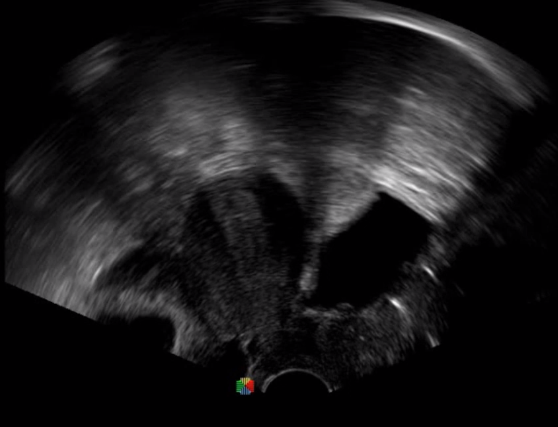

取卵臨床圖

傳統(tǒng)腔內(nèi)探頭采用直柄設(shè)計,在搭配穿刺架使用時,手術(shù)空間小,不易操作;生殖專用的曲柄探頭,探頭柄采用彎曲成角度設(shè)計,可實現(xiàn)監(jiān)視、取卵兩不誤,搭載穿刺架時,可以清晰顯示穿刺針的進(jìn)針過程、深度和位置,實時監(jiān)視取卵全過程,保障取卵操作精準(zhǔn)與安全。